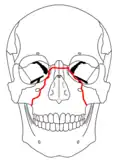

- The Le Fort III fracture (transverse fracture) occurs at the level of the skull base, resulting in complete craniofacial separation of the midface from the base of the skull.[2][3] The fracture line extends through the zygomatic arch, the pterygoid plates, the lateral and medial orbital walls, the nasal bones, and the nasal septum.[2][5] The salient feature of these fractures is that they invariably involve the zygomatic arch, or cheek bone.[5] These are the most extensive of the Le Fort fractures and often require open surgical intervention.[3]